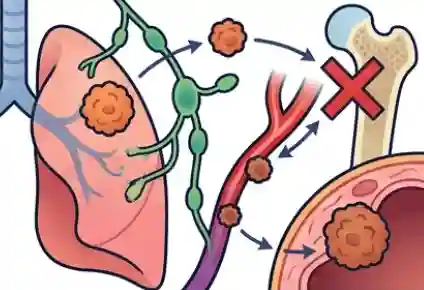

A landmark 2016 meta-analysis published in The Journal of Pain and Symptom Management found that 55% of patients undergoing anti-cancer treatment experience pain, rising to nearly 70% in advanced or metastatic disease. And in a finding that should shame every healthcare system, nearly half of all cancer patients globally receive inadequate analgesia.

India’s cancer pain crisis is a story of multiple compounding failures of awareness, of access, of stigma, and of a healthcare system where pain specialists are bypassed in the rush from oncologist to hospital, and back again. Consider this: India accounts for nearly 8% of global cancer deaths, yet consumes less than 1% of the world’s medical morphine. That gap is not a reflection of less pain it is a reflection of how catastrophically undertreated that pain is.

There is a dangerous and widely held assumption that once cancer is in remission, the pain disappears with it. For a significant proportion of cancer survivors worldwide and in India, where millions have completed treatment this assumption is cruelly wrong.

Common chronic pain syndromes in cancer survivors include post-mastectomy pain syndrome, chemotherapy-induced peripheral neuropathy, radiation fibrosis and plexopathy, lymphoedema, hormone-therapy-induced musculoskeletal pain, and entirely unrelated age-related conditions such as osteoarthritis and disc disease that deserve their own assessment and treatment.

India has an estimated 3–5 million cancer survivors — a number growing rapidly with improving treatment outcomes. The majority have ongoing pain that is undertreated. A dedicated cancer survivor pain assessment at IBAP Clinics can provide these patients with the specialist attention they deserve.